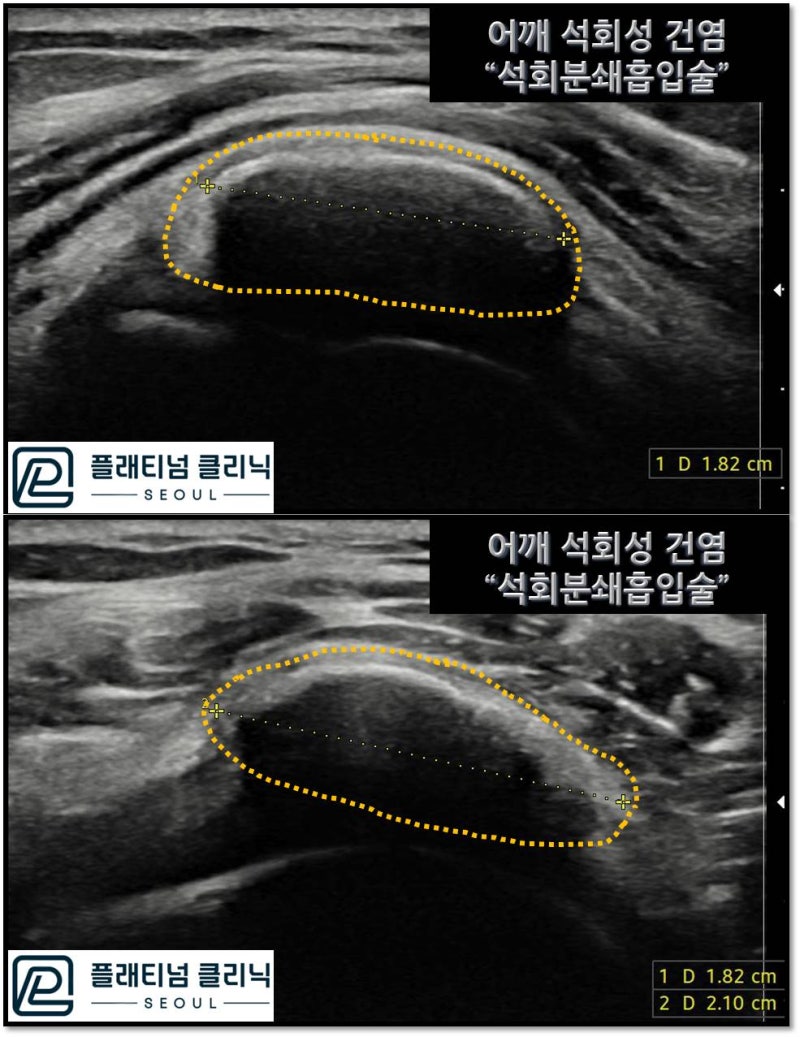

초음파 검사를 해서 크기를 살펴보니 길이 1.8cm, 폭 2.1cm 크기의 석회가 관찰됩니다. 극상근의 폭이 동양인의 경우 2.4~3.0cm 정도되는데 거의 극상근 전체에 걸처 석회가 형성된 것이 관찰됩니다. 이 어마어마한 석회성 건염을 석회분쇄흡입술 로 치료하였습니다. 석회분쇄흡입술에 대해서는 아래 링크를 참고하시기 바랍니다. https://blog.naver.com/9690067/222772754214